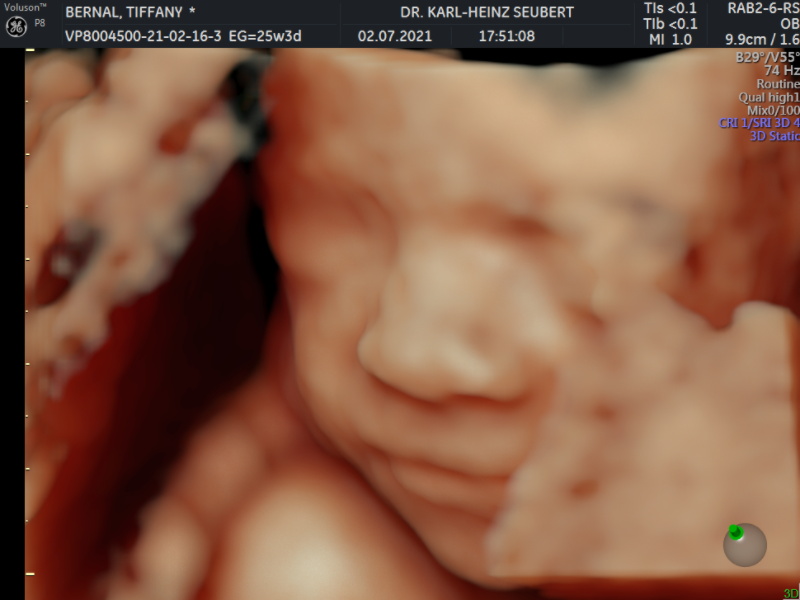

- Ultrasonido 2D, 3D, 4D incluidos

- Cuento con ultrasonido de ultima generación Voluson P8. con alta resolución, ultrasonido 4D incluido sin costo extra. Ultrasonido 4D

ULTRASONIDO 4D INCLUIDO